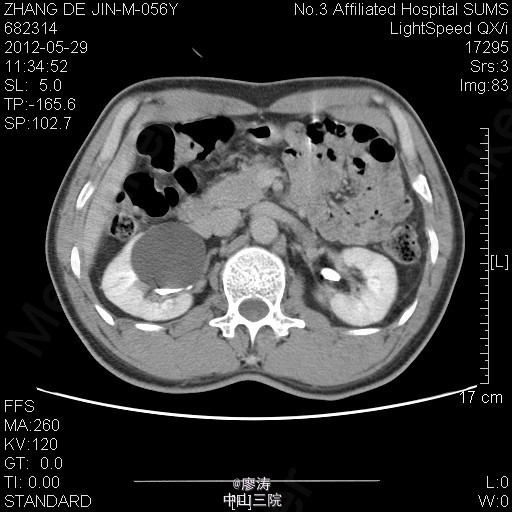

患者男,56岁,因腰痛2年到当地医院检查,当地医院彩超提示:右肾下部无回声区,考虑肾囊肿可能性大,右肾上盏局限性积液,余未见明显异常。为进一步治疗来我院就诊,行腹部CT检查提示右肾巨大囊肿,压迫右侧肾盂及中下盏。

腹部CT检查提示右肾巨大囊肿

诊断:右肾巨大囊肿 处理:行单孔腹腔镜下右肾囊肿去顶术 手术过程:麻醉成功后,取左侧卧位,常规消毒铺巾。在右侧髂脊上腋中线两横指作长约3.0cm横行切口,分离后建立单孔操作系统。分离腹膜外脂肪及肾旁脂肪,打开肾周筋膜,用超声刀仔细分离肾周脂肪,进入肾后间隙,于肾门附近、靠近肾盂内下方位置寻及肾盂旁囊肿,肾盂受压,PK刀分离囊肿周围脂肪,囊肿壁部分显露。PK刀打开囊肿,流出淡黄液体约40ml。吸尽囊液,在距离肾实质约6mm处剪除视野可见囊肿壁,范围约3cm,标本送病理检查。检查囊肿切缘无活动性出血后,拔出自制单孔设备,原切口放置橡胶引流管一条。逐层缝合切口。术毕,病人安返病房。术中出血约50ml。